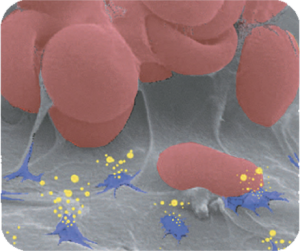

Osteointegración

En estudios preclínicos, los implantes T3® con superficie DCDR de ZimVie® han demostrado un aumento de la fuerza de integración durante la fase de cicatrización comparada con superficies con topografías menos complejas.

Mitigación del riesgo de Peri-implantitis

El implante T3® de ZimVie® utiliza la probada tecnología de superficie OSSEOTITE® en la zona coronal del implante. En el estudio realizado, con cinco años de seguimiento, la superficie con doble grabado ácido del implante OSSEOTITE® no presentó mayor riesgo de peri-implantitis ni de complicaciones del tejido blando, en comparación con superficies mecanizadas.*

Superficie Osseotite®

LA SUPERFICIE MÁS PROBADA DEL MUNDO

Un extraordinario índice de éxitos probado por los excelentes resultados obtenidos en numerosos estudios clínicos en curso.

Pero las razones que han llevado a dicho éxito son igualmente convincentes. Este éxito se debe a la realización de investigaciones intensivas que han permitido conocer a fondo el proceso de cicatrización, así como al diseño patentado de OSSEOTITE®, responsable de su increíble eficacia clínica.